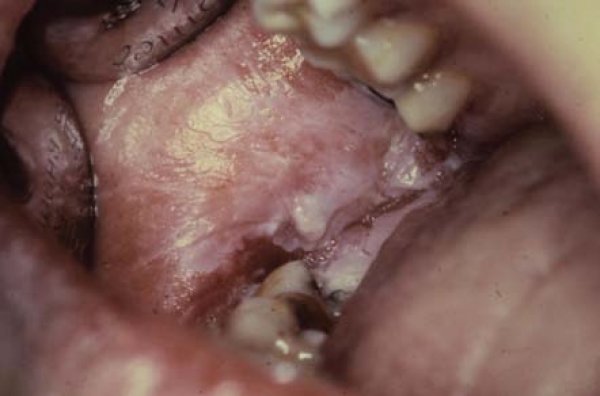

Dr. Betül İLHAN, Prof. Dr. Hülya ÇANKAYA, Prof. Dr. Pelin GÜNERİ

Ağız boşluğu ve farenkste en sık karşılaşılan malignansi, her yıl yaklaşık 350,000 kişide belirlenen ve dünyada 68,000 kişinin ölümüne neden olan (1) skuamöz hücreli karsinomadır (2,3).

Doç. Dr. Filiz Namdar Pekiner

Sir James Paget tarafından 1851’de “leukokeratosis”, 1870’de ise “icthyosis” olarak isimlendirilen oral lökoplaki

(OL) ‘nin ilk ve tam olarak tanımı 1877’de Macar dermatolog E. Schwimmer tarafından tersiyer dönem sifilizde dildeki beyaz değişiklikleri anlatmak amacıyla yapılmıştır (1-4).